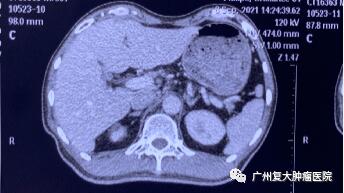

为减轻肿瘤负荷,改善生活质量,延长患者生命,经患者及家属同意,我院牛立志院长为其实行胰腺肿瘤、肝脏肿瘤不可逆电穿孔治疗,术中以胰腺肿瘤、肝脏10个病灶为靶区消融。术后联合化疗加免疫药物治疗进一步改善治疗效果。

术后一周检查发现,身体各项指标逐步恢复正常。与之前相比,上腹部MRI图像提示胰腺、肝脏肿瘤中心大部分坏死。术后一年复查显示,肿瘤缩小,得到较好的控制。

▲术后一周

▲术后一年